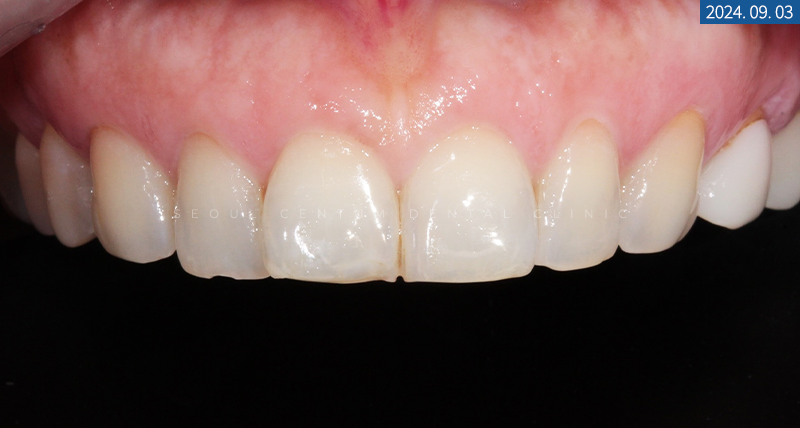

환자분께서 치아 형태와

색조를 변경하기를 원하시는

#13~23번 치아 중 대부분은

치질을 0.1mm가량 삭제하는

무삭제라미네이트가 가능하지만

#11, #21번 치아는 Rotation이 심한 것으로 확인되어

0.3~0.5mm의 평활면을 절삭할 수 있다고

충분히 설명해 드린 후 술식을 진행하게 되었습니다.

그런 후 구내 사진을 찍고

접착면을 고르게 다듬으면서 절삭하기 위해

버를 사용하여 다듬어드렸는데요.

환자분께서 최소 삭제를 원하셨기에

돌출과 회전감이 심한 #11, #21번 치아는

치질 삭제를 0.3mm 하고

나머지 #13~23번 치아는

0.1mm 미만으로 절삭해 드렸습니다.